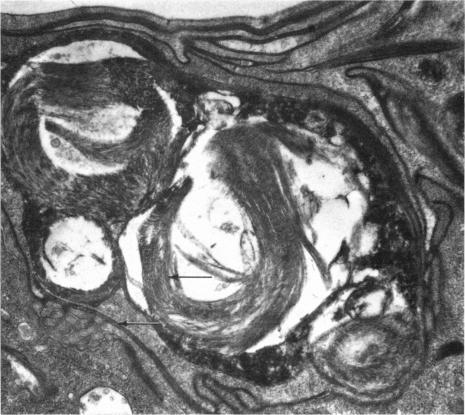

The development of the chick tertiary bronchus. II. The origin of the surface lining system.

J Anat. 1972 Dec;113(Pt 3):325-40.